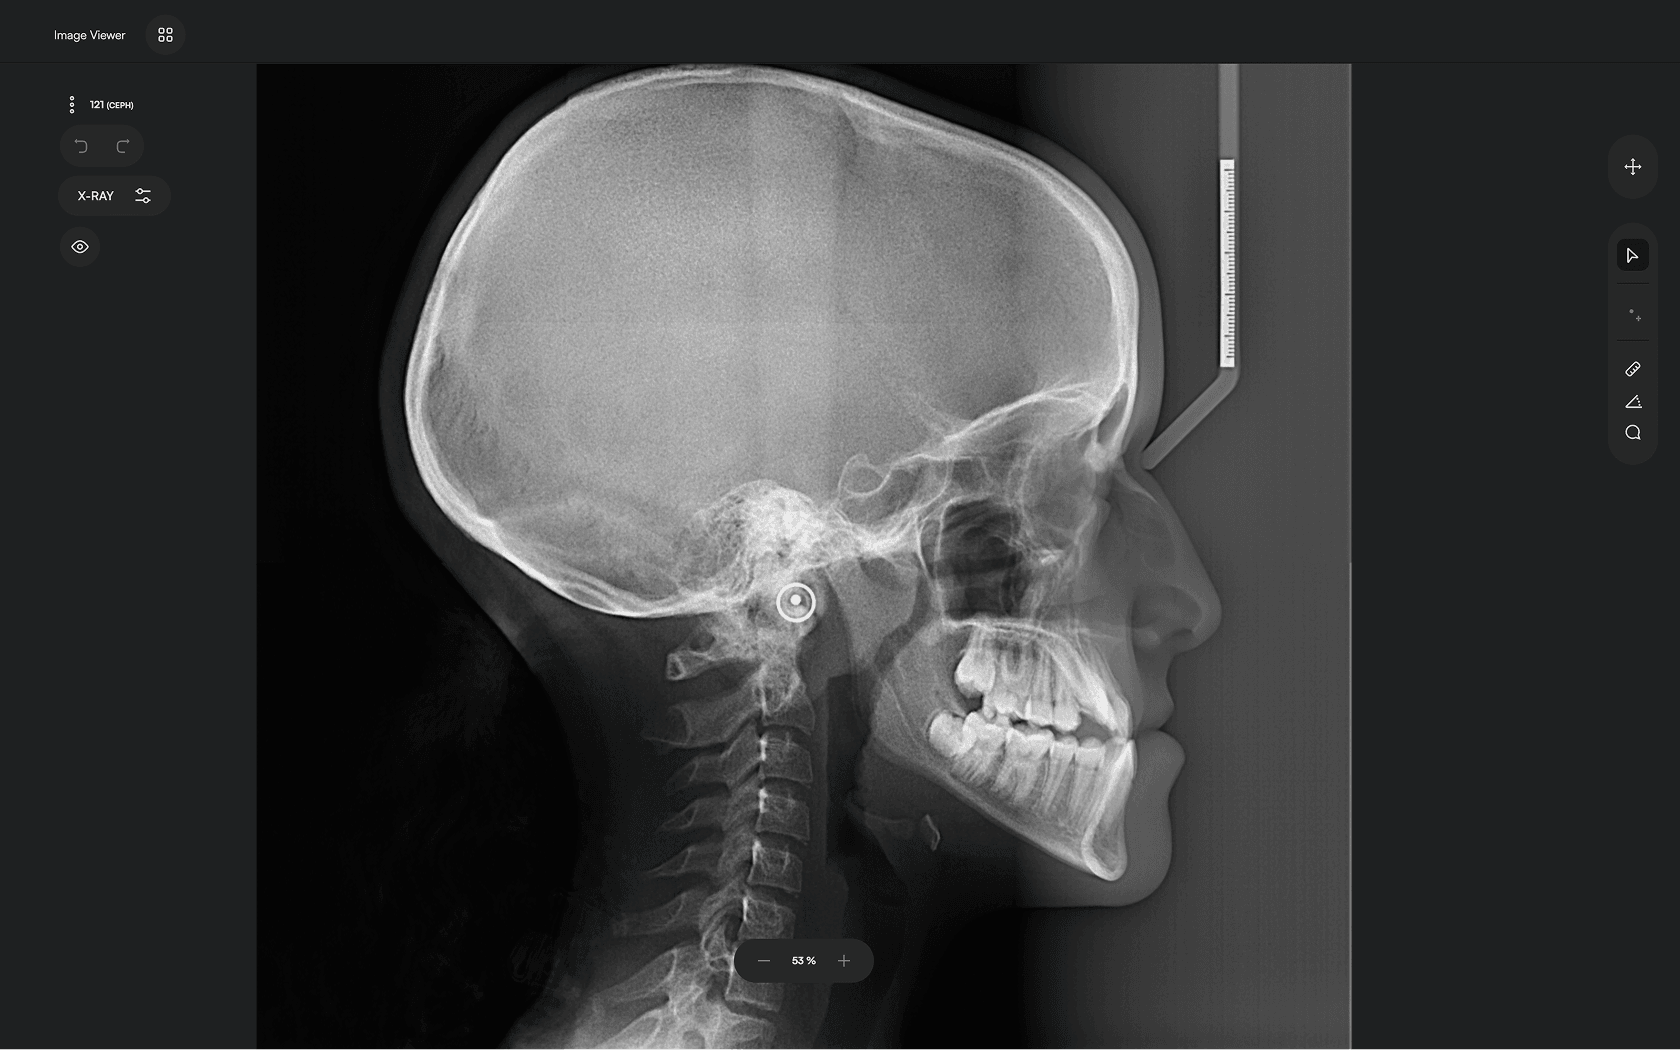

AI-driven Automated Lateral

Cephalometric Tracing

Accurate. Fast. Effortless.